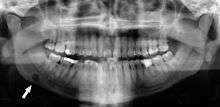

Panoramic radiographs have the capability to demonstrate a portion of the neck and display atheromas (calcifications in the carotid artery) which are an indication of both local and generalized (systemic) atherosclerosis. Atherosclerosis of the coronary arteries leading to myocardial infarction (heart attack), and atherosclerosis of the carotid artery leading to stroke are the number one and number three most common causes of death in the United States.[5]

There is interest to look at panoramic radiographs as a screening tool, however further data is needed with regards if it is able to make a meaningful difference in outcomes.[6]

Epidemiology: General Public and High Risk Groups

Additional research projects have further determined the prevalence rate of these atheromas in the general population (3-5%)[7] and among high-risk groups (over 25% in: recent stroke victims,[8] individuals with obstructive sleep apnea syndrome,[9][10] postmenopausal women,[11] type 2 diabetics,[12][13] individuals with dilated cardiomyopathy,[14] and among individuals who have received radiotherapy directed at the neck,[15][16]). These findings have been corroborated by other several other researchers.[17][18][19][20]

Atherosclerosis is attributed to risk factors that include cigarette smoking, hyperlipidemia, obesity, diabetes mellitus, and hypertension (high blood pressure). These factors, however, do not fully account for the risk of disease. Atherosclerosis has been conceptualized as a chronic inflammatory response to endothelial cell injury[21] and dysfunction possibly arising from chronic dental infection. In 2010, using the previously validated Mattila panoramic radiographic index to quantify the totality of dental infection (i.e., periapical and furcal lesions, pericoronitis sites, carious tooth roots, teeth with pulpal caries, and vertical bony defects), Friedlander’s group determined that individuals with carotid artery atheromas on their panoramic radiographs had significantly greater amounts of dental infection/inflammation than atherogenic risk-matched controls devoid of radiographic atheromas.[22][23] While the Mattila index had been previously used to relate the extent of dental infection to coronary artery disease, this research is the first to link the full range of dental disease that it measures to panoramic radiographs evidencing calcified carotid artery atherosclerosis.